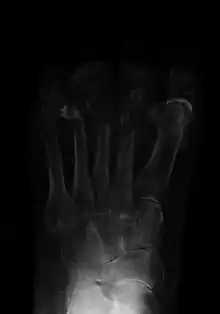

![]() | |

| Osteomyelitis of the 1st toe | |